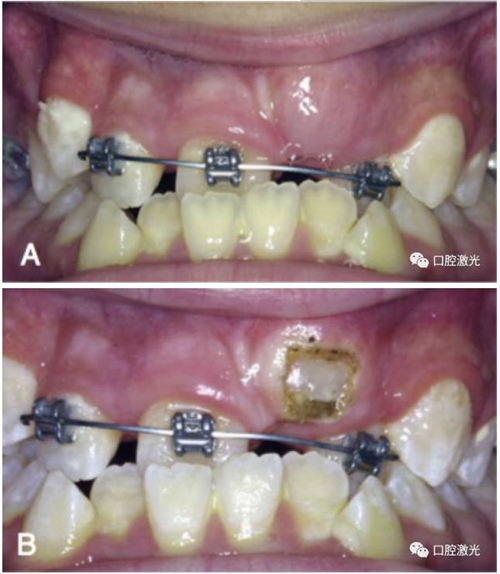

獲得理想的托槽粘接位置

正常情況下,理想的托槽粘接位置為牙冠的中心位置。如果要達到這一目的,正畸牙醫(yī)首先需要能夠從視覺上觀察清楚牙冠的整體形態(tài)。如果存在牙齦覆蓋、遮擋的情況,就很難達到這一目的。這時,簡單的激光牙齦切割就可以很好的增加牙冠的暴露程度,達到更加準確的粘接托槽的目的,從而也就加快了整個正畸療程的速度。通過下圖的病例可以看到,不僅患者節(jié)約了數(shù)月的等待時間,同時也創(chuàng)造了一個干凈的口腔環(huán)境,降低了在后續(xù)的正畸治療中可能導致牙齦增生的風險。

治療前

激光牙齦切割后暴露更多的上前牙便于粘接托槽

當天粘接托槽后即刻

4周后即可見明顯效果